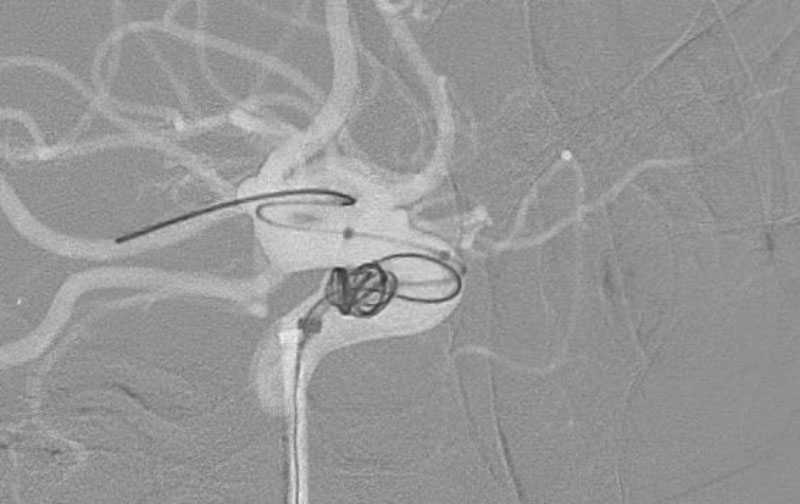

右内頚動脈後交通動脈

分岐部動脈瘤破裂

No.1593 手術中